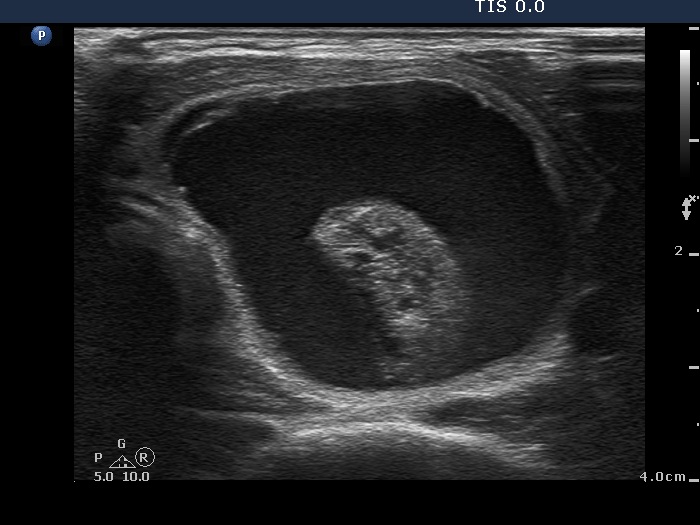

Right lobe, longitudinal scan

Right lobe, horizontal scan. The lesion significantly increased in size. The inhomogeneous mass might correspond to necrotic material.